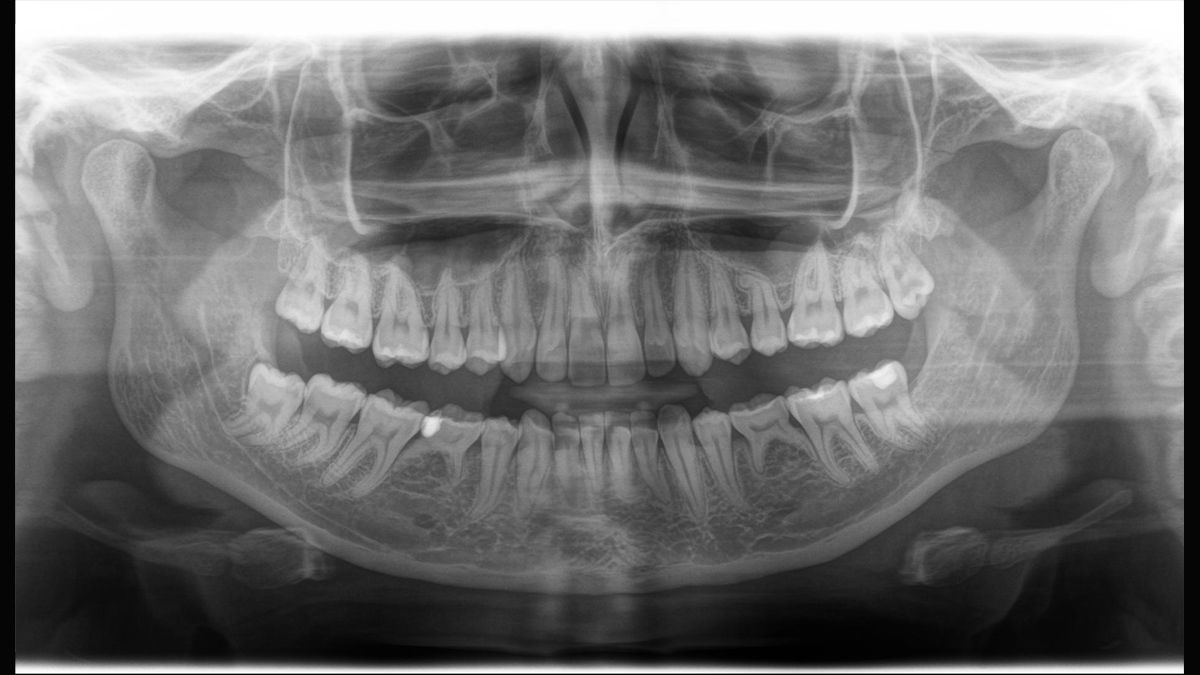

Tecnología Sharp Layer (SL)

La tecnología SL le permite generar multiples imágenes durante una única rotación. Los fragmentos con mejor enfoque se combinan automáticamente para formar una imagen de rayos X con nitidez incomparable (ideal para observar piezas multiradiculares).

Direct Conversion Sensor

La tecnología DCS convierte los rayos X directamente en señales eléctricas sin pérdida de información debida a la conversión de la luz. Permite obtener imágenes de radiografía panorámicas de elevado contraste con una calidad excepcional.

Algoritmo de software ASTRA

ASTRA mejora considerablemente la calidad de las imágenes panorámicas 2D y cefalométricas. Este algoritmo de reconstrucción estructurado anatómicamente genera una imagen con mayores contrastes sin la aparición de bordes indefinidos.